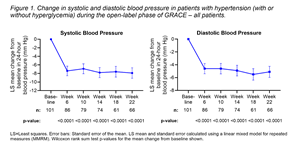

The risk of fibroid diagnosis is increased among patients with untreated and new-onset hypertension compared to those taking antihypertensive treatment, according to a recent study published in JAMA Network Open. Takeaways Untreated or new-onset …